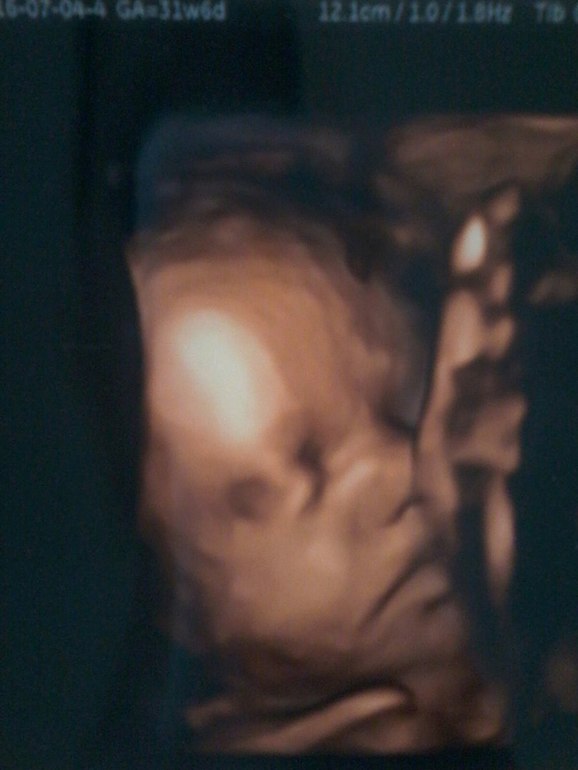

Последнее плановое УЗИ :)

Вопросы про УЗИ, обследования и анализы: что, где, как, когда?Вчера делали последнее УЗИ. Насмотрелись на сынулю ) Эх он там чудит ))) Руками за пятки хватает, ручками и ножками машет, не удивительно, что мне так больно бывает )

Нам для прикола даже ресницы измерили, 3 мм уже ) Щекастенький уже, но очень грустный, видно скучно ему там...

По росту опережает на недельку срок. Весим уже 1840 гр.